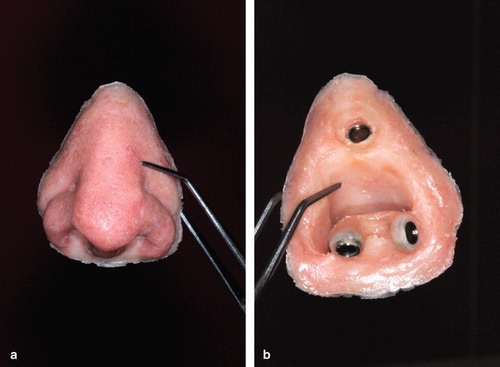

Zygomatic Implants supporting facial prostheses really improve the quality of life for patients following rhinectomy. Here is a case from a group in Norway demonstrating the secondary placement of zygomatic and dental implants in order to retain a nasal prosthesis, here with the use of small magnet abutments. The complexity of undertaking this secondarily in our view with computerised planning and surgigide construction together with the delay in providing a retentive solution is the reason why our approach is always to place implants at the time of resective surgery.